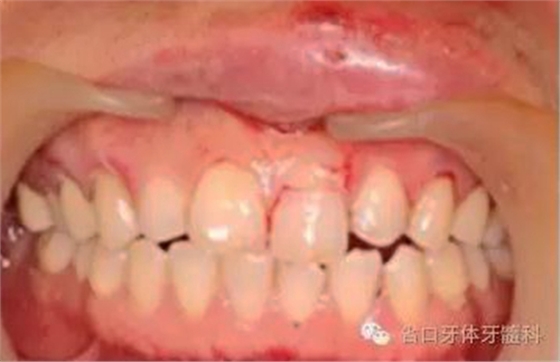

圖2. 術前口內(nèi)照片,21/冠折。

圖3. 術前X線片